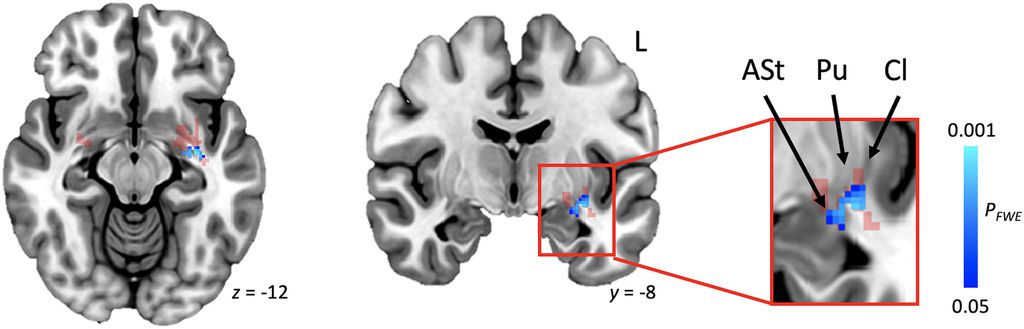

Publicado na revista Brain, o estudo é o primeiro a relacionar os diferentes tipos de gagueira a uma única região disfuncional no cérebro. No epicentro da condição, está a estrutura conhecida como putâmen, que regula a função motora. Também são afetadas a amígdala e o claustro. As três estruturas compõem parte do que é conhecido como telencéfalo.

“O putâmen regula a função motora, e a amígdala regula as emoções. O claustro, por sua vez, atua como um nó [ponto de conexão] para diversas redes cerebrais e retransmite informações entre elas”, detalha Juho Joutsa, professor de neurologia da Universidade de Turku e autor do estudo, em nota.

Entre os voluntários, estavam pessoas que desenvolveram a gagueira ainda na primeira infância e aqueles que desenvolveram a condição na fase adulta. Isso pode ocorrer após um Acidente Vascular Cerebral (derrame). Em ambos os grupos, os pacientes tinham as mesmas mudanças estruturais em torno da estrutura conhecida como putâmen.